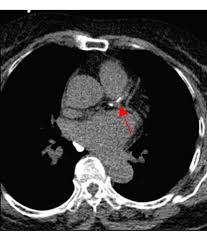

3. 진단 방법 – CAC 스코어

- 비침습적 **관상동맥 칼슘 스캔(칼슘 스코어 CT)**로 Agatston score 산출 :contentReference[oaicite:6]{index=6}.

- 0 = 이상 없음, 1–99 = 경증, 100–399 = 중등도, ≥400 = 중증으로 분류되며, 점수가 높을수록 심혈관 위험이 증가합니다 :contentReference[oaicite:7]{index=7}.

- 중등도 이상일 경우 관상동맥 협착 위험이 높으며, 추가 정밀검사 및 적극 치료가 필요합니다 :contentReference[oaicite:8]{index=8}.

- CT 스캔은 빠르고(약 15분), 고해상도이며, 진단·예후 판단에 유용합니다 :contentReference[oaicite:9]{index=9}.